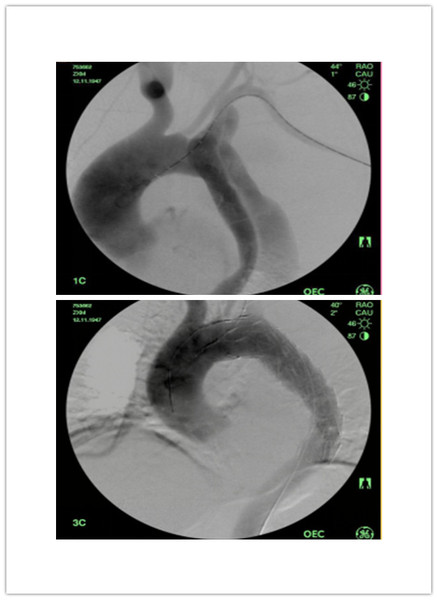

上图为治疗前 下图为植入支架后

对于急性夹层的患者,无论我们进一步要采取何种治疗手段,首先应进行相应的保守治疗:控制血压,控制疼痛。通常需要应用强有力的药物,如降压的硝普钠,镇痛的吗啡等。而对于情况危急的患者,往往需要急诊气管插管、呼吸机辅助呼吸,进行急诊抢救手术,但也意味着极高的风险和死亡率。

在患者情况适当稳定后,治疗方式的选择主要根据夹层的类型而定。就目前的治疗现状而言,对于Stanford B型主动脉夹层,以微创腔内治疗为主。治疗的依据包括以下情况,或者说手术适应症:夹层持续扩大,表现为主动脉夹层直径快速增大、范围迅速增加、胸腔出血、疼痛无法控制;或是主动脉的主要分支,如肠系膜上动脉、肾动脉缺血。